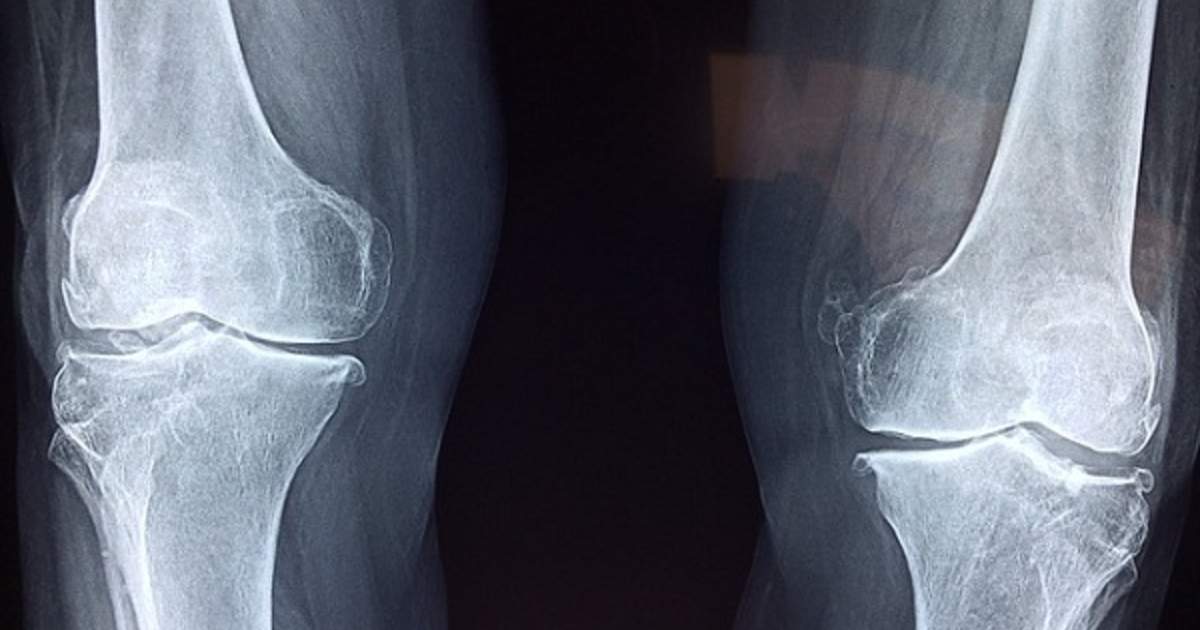

Stenosis is defined as a narrowing in the spine. There are two types: central stenosis and neural foraminal stenosis. Central stenosis refers to narrowing of the spinal canal that holds the spinal cord, and neural foraminal stenosis involves narrowing of the hole the spinal nerves transverse when they exit the spine. This narrowing can be caused by numerous conditions and is often multifactorial. The neural canal is formed by a vertebra above and below and the disc between them. It is naturally comprised of bone, discal material, ligaments, as well as the exiting nerve and blood vessels. Enlargement of any of these structures, additional material in the canal, and reduction of the canal size by encroaching entities all contribute to neural foraminal stenosis.